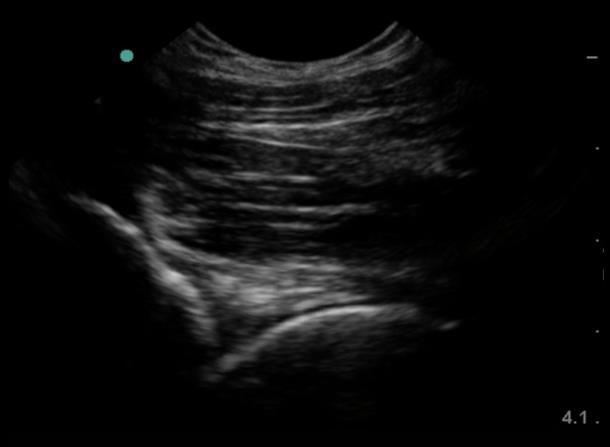

股関節大腿骨頭寛骨の画像